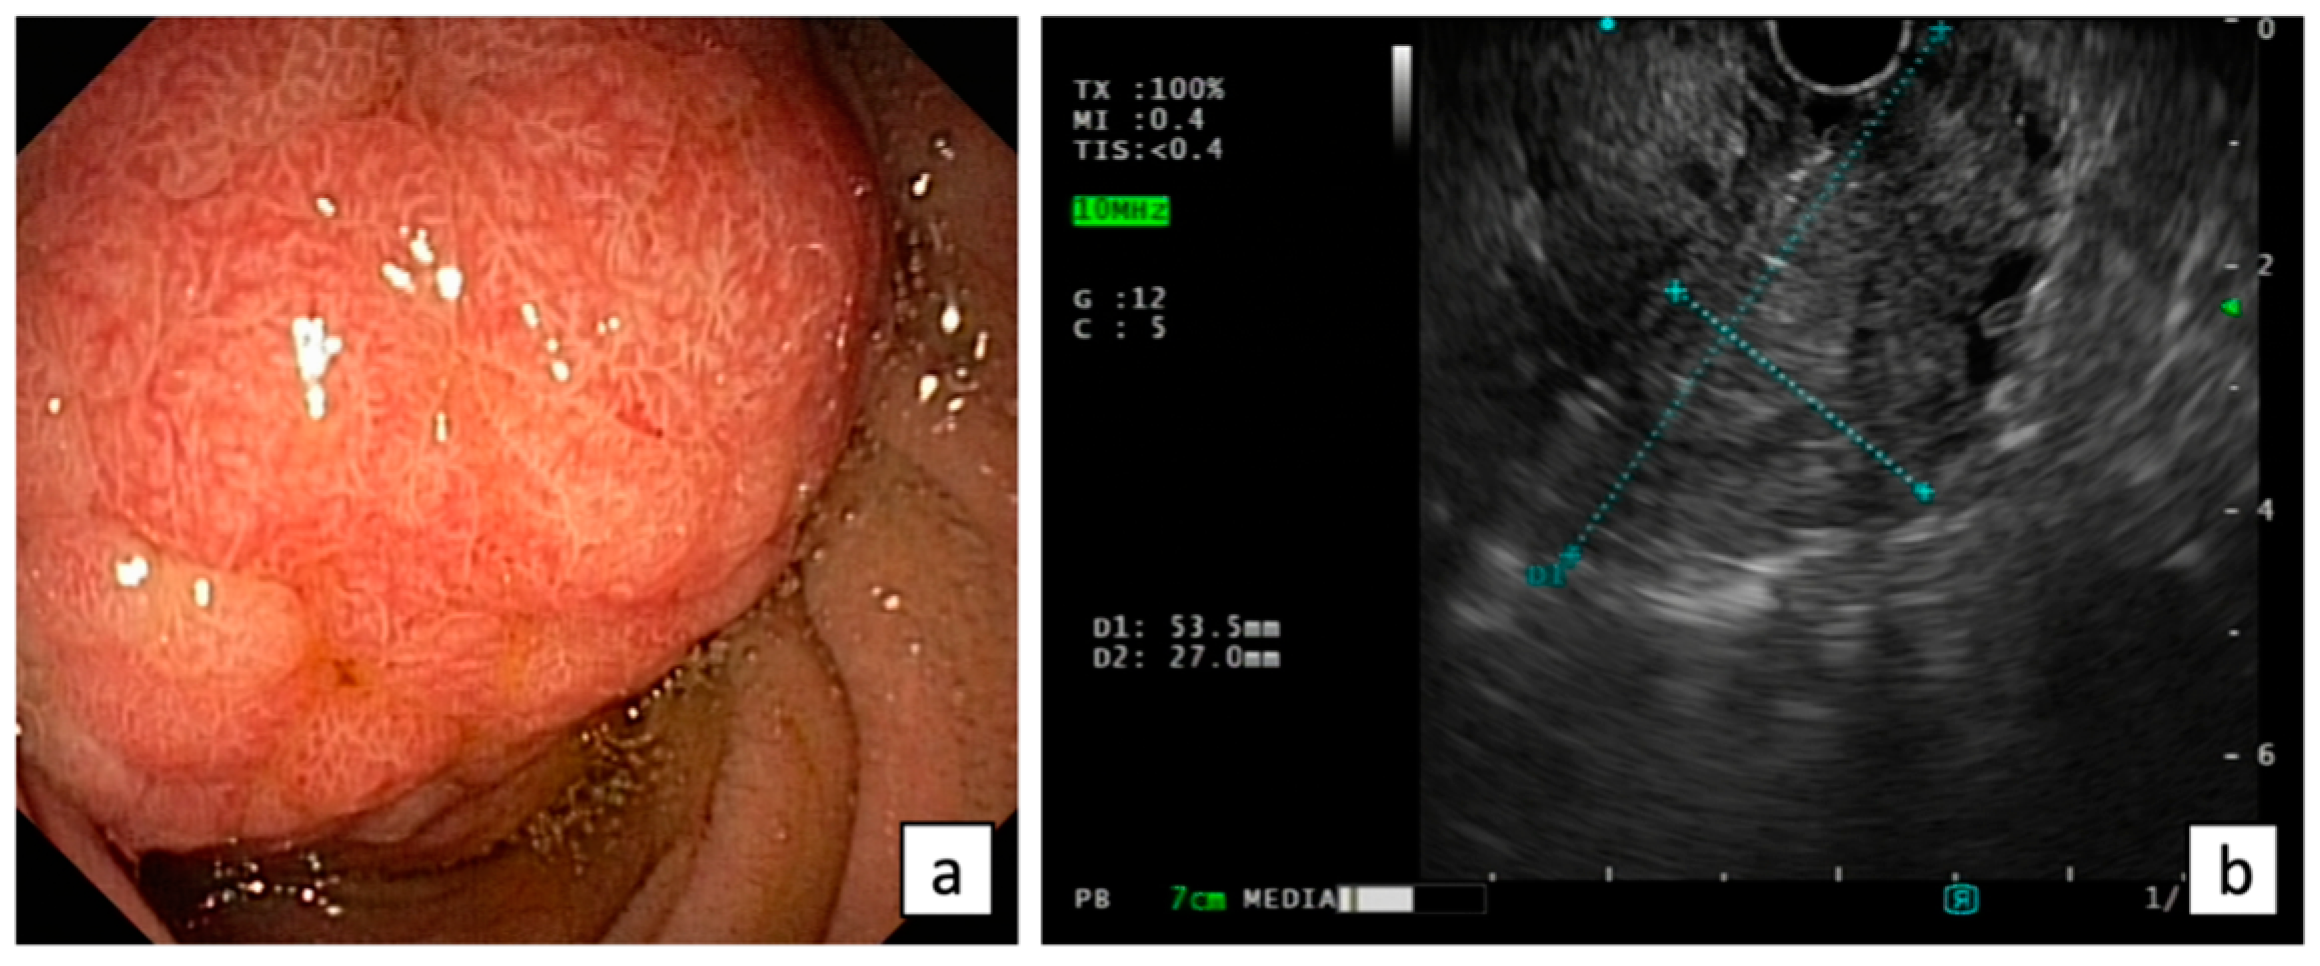

Endoscopic evaluation of ANLs may be challenging using a forward-viewing endoscope. The European Society of Gastrointestinal Endoscopy (ESGE) considers the visualization of the papilla as a research priority for a complete high-quality endoscopy [16]. Thus, cap-assisted upper endoscopy should be indicated when the major papilla is not seen by a gastroscope, but a side-viewing duodenoscopy is recommended for the optimal visualization of the papilla and the assessment of the feasibility of endoscopic resection in presence of ANLs [17] (Figure 1).

Endoscopic (a) and EUS (b) evaluation of ANLs.

Endoscopic ultrasound (EUS) plays a crucial role in the ANL evaluation, providing an accurate assessment of the size, location, and characteristics of the lesions, including the staging of the depth of tumor invasion into the surrounding tissues such as duodenal wall, biliary duct, pancreatic duct, and pancreatic parenchyma, and the involvement of local lymph nodes, according to the latest TNM classification (Figure 1).